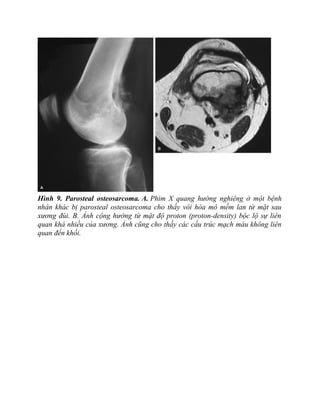

Hình 9. Parosteal osteosarcoma. A. Phim X quang hướng nghiêng ở một bệnh

nhân khác bị parosteal osteosarcoma cho thấy vôi hóa mô mềm lan từ mặt sau

xương đùi. B. Ảnh cộng hưởng từ mật độ proton (proton-density) bộc lộ sự liên

quan khá nhiều của xương. Ảnh cũng cho thấy các cấu trúc mạch máu không liên

quan đến khối.